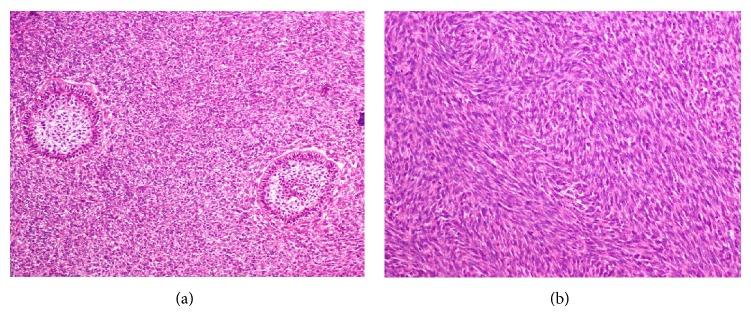

Ameloblastic fibrosarcoma is an uncommon odontogenic tumor composed of a benign epithelial component and a malignant ectomesenchymal component most frequently seen in the third and fourth decades of life. It mainly presents as a painful maxillary or mandibular swelling. Radiographs show a radiolucent mass with ill-defined borders. Radical surgical excision and long-term follow-up are the suggested treatment. We report the case of a 22-year-old female with a 2-month history of an asymptomatic swelling in her left mandible. Examination revealed an exophytic growth measuring 3 × 3 cm extending from the mandibular left first premolar to the second molar. The patient underwent a left hemimandibular resection. Histopathological examination revealed a biphasic tumor composed of inconspicuous islands of benign odontogenic epithelium and an abundant malignant mesenchymal component with marked cellularity, nuclear pleomorphism, hyperchromatism, and moderate mitotic figures with clear margins; one year after the surgical procedure, the patient is clinically and radiologically disease-free.

成釉细胞纤维肉瘤是一种罕见的牙源性肿瘤,由良性上皮成分和恶性外胚间叶成分组成,最常见于30至40岁。它主要表现为上颌或下颌的疼痛性肿胀。X线片显示边界不清的透射性肿块。建议的治疗方法是根治性手术切除和长期随访。我们报告一例22岁女性,左下颌无症状肿胀2个月。检查发现一个从左下颌第一前磨牙延伸至第二磨牙的外生性肿物,大小为3×3厘米。患者接受了左半下颌骨切除术。组织病理学检查显示为双相性肿瘤,由不明显的良性牙源性上皮岛和丰富的恶性间叶成分组成,细胞丰富,有明显的核多形性、核深染,有中度核分裂象且边界清晰;手术后一年,患者临床和影像学检查均无疾病。